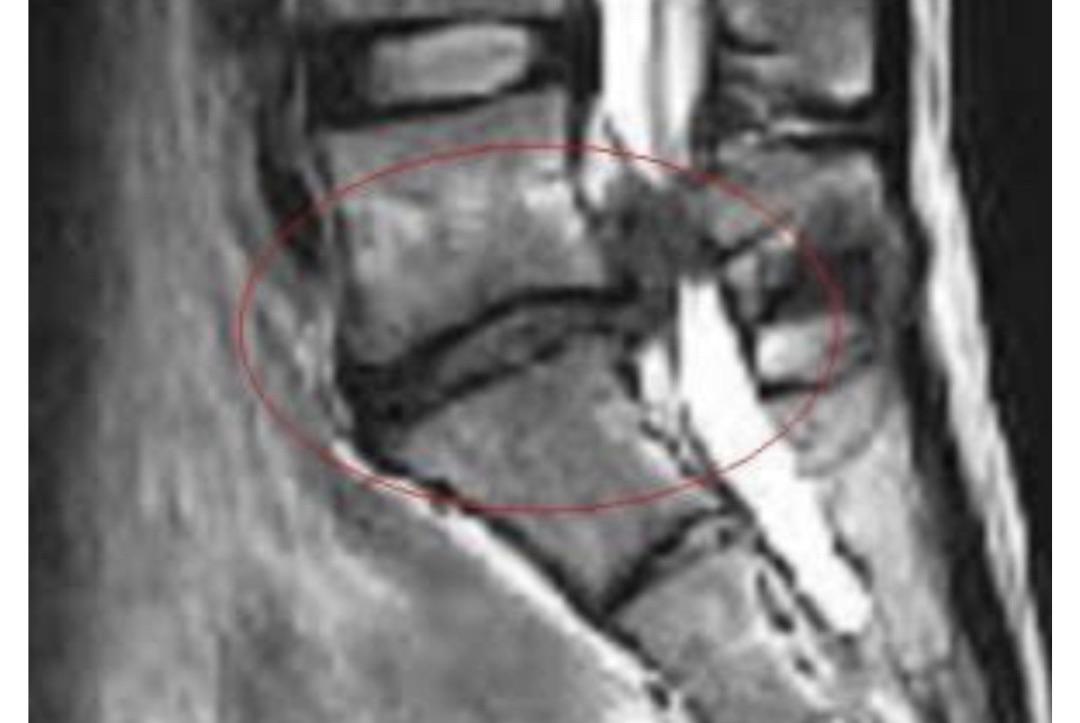

椎間板ヘルニアでの痺れが

良くなりました!

A腰から左足にかけ痛みと痺れが酷く、立ち仕事なのですが長く立っていられず休み休みになってしまう中でこのまま仕事を続けられるのか、生活はしていけるのか毎日不安でした。

A整形外科で痛み止めをもらって飲んでいました。痛みがなかなか良くならずこのままだと手術の可能性もあると言われていました。

A痛みも痺れも良くなり助かりました!

仕事も出来る様になった事で生活の心配もなくなり、手術をしなくても済んだ事にホッとしています。